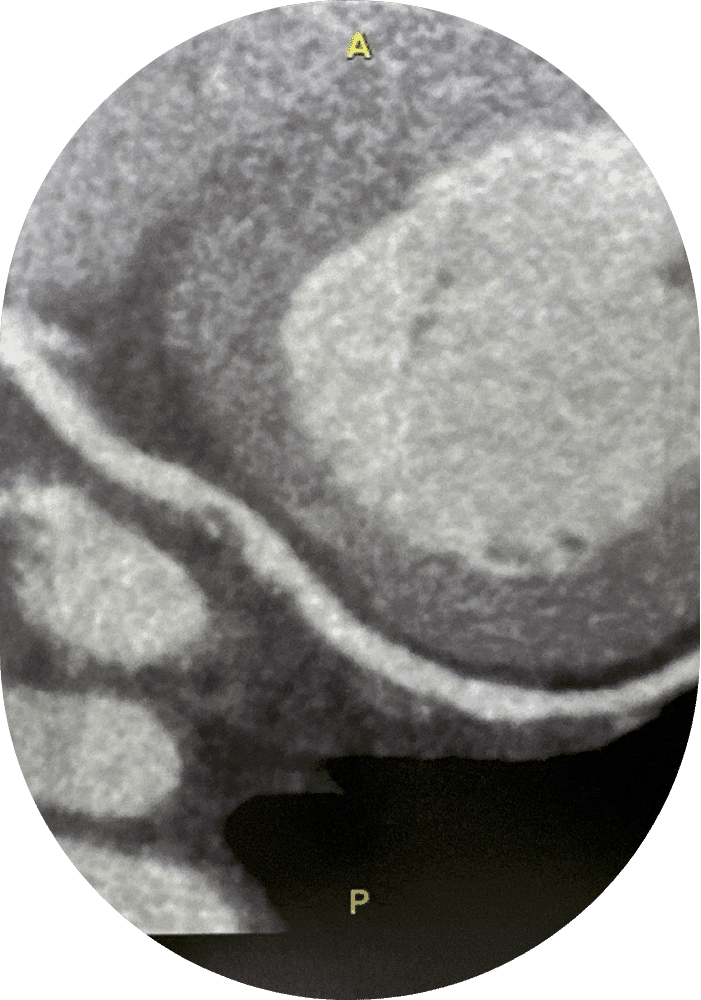

Évaluation anatomique endo-coronaire

Cette appellation regroupe deux types d’examens dont le but est d’obtenir des images depuis l’intérieur des artères coronaires (vaisseaux sanguins qui irriguent le cœur). Ils permettent d’apprécier la santé des coronaires (si des plaques ou des rétrécissements sont présents), et peuvent être prescrits pour évaluer les résultats à la suite de la mise en place d’un stent par exemple.

L’échographie endo-coronarienne (IVUS) est un examen qui fait appel à des ondes ultrasonores et permet l’obtention d’images précises pour analyser de façon plus fine la paroi des artères coronaires (calcifications…) et les implantations de stents.. L’ OCT (Optical Coherence Tomography) quant à elle est une technique de pointe relativement récente, qui permet également d’obtenir des images en coupe avec une très grande définition.

CARDIO INTER - Évaluation anatomique endo-coronaire